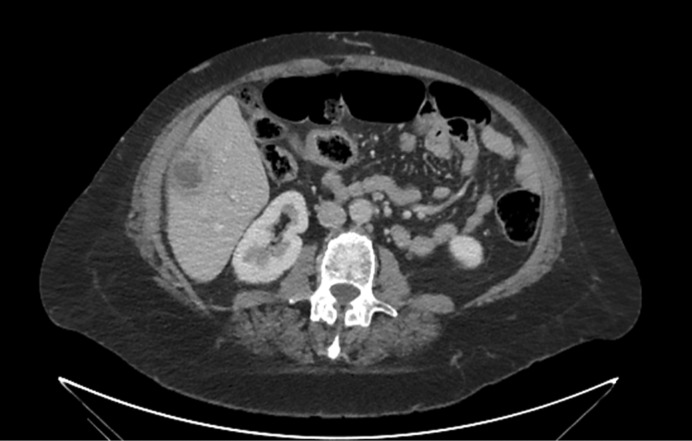

Introduction: Aseptic hepatic abscesses are a highly uncommon phenomenon and even more rare in the spectrum of extraintestinal manifestations of inflammatory bowel disease. Part of the spectrum of "neutrophilic disease," both the pathogenesis and the optimal management of these aseptic abscesses remain unclear. In the context of inflammatory bowel disease, sometimes these abscesses appear despite normal endoscopic findings.

Case presentation: We describe a highly uncommon case of aseptic hepatic abscess formation in a patient with inflammatory bowel disease.

Abstract Image